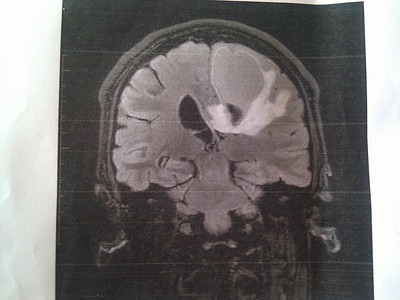

뇌종양에 대한 방사선 요법은 고에너지 방사선을 사용하여 암 세포를 죽이고 뇌의 종양을 축소시키는 암 치료의 한 유형입니다. 뇌종양은 양성(비암성) 또는 악성(암성)일 수 있습니다. 뇌종양에 대한 방사선 요법의 목표는 종양을 둘러싼 건강한 뇌 조직의 손상을 최소화하면서 가능한 한 많은 암세포를 파괴하는 것입니다. 다양한 유형의 뇌종양, 사용할 수 있는 다양한 방사선 요법 옵션 및 이 치료의 잠재적인 부작용에 대해 알아보겠습니다.

원발성 뇌종양은 뇌에서 발생하는 종양입니다. 이 종양은 양성일 수도 있고 악성일 수도 있습니다. 원발성 뇌종양의 가장 일반적인 유형은 신경아교종, 수막종 및 뇌하수체 선종입니다.

신경아교종은 뇌의 신경아교세포에서 발생하는 종양입니다. 이러한 종양은 기원한 신경아교세포의 유형에 따라 다른 아형으로 더 분류될 수 있습니다. 가장 흔한 유형의 신경아교종은 교모세포종(glioblastoma)이라고 합니다.